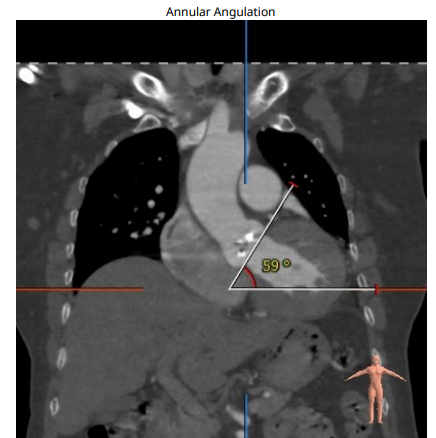

术前周浩教授带领团队对这位患者进行了详细的分析,从CT分析结果显示,患者的瓣环直径为25.1mm,结合患者瓣叶钙化等情况,符合美敦力Evolut PRO 29mm瓣膜选型要求。难点在于患者左右瓣叶钙化严重,钙化积分达到了1500,经讨论决定术中进行23mm球囊预扩张,保证系统顺利跨瓣及释放。术中采用了全球领先的Cusp Overlap瓣膜植入技术,实现更精准地定位瓣膜深度,减少对患者传导系统的影响。

180bpm下置入23mm球囊扩张,沿导丝送入美敦力Evolut PRO经导管主动脉瓣膜系统,采用美敦力独有的commissural alignment技术,最大程度保护冠脉。递送系统顺利送入动脉系统并顺利过弓跨瓣,在最终目标位置完美释放,瓣膜立即工作。展开形态良好,无瓣周漏,无冠脉阻挡,无传导阻滞发生,术后无跨瓣压差,血液动力学稳定,手术圆满成功。